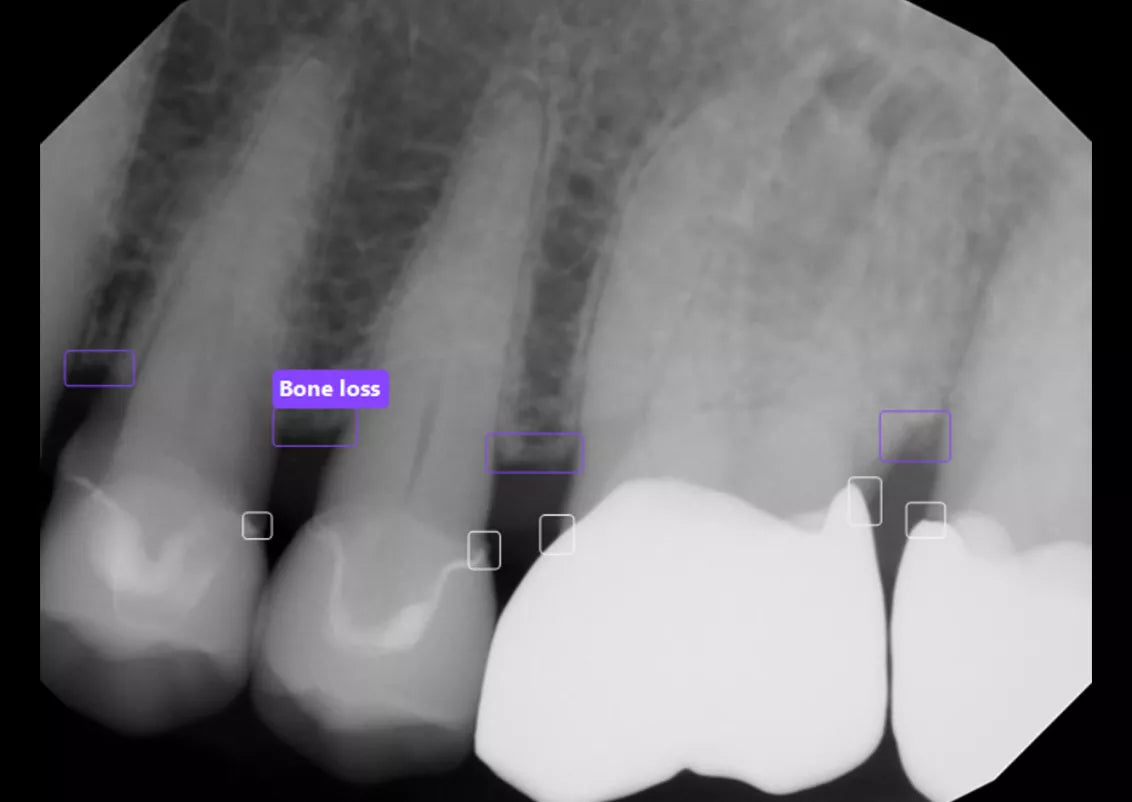

Built into DEXIS™ Imaging Suite Software, the DEXassist Solution provides assisted intelligence with a single click. This new solution enables users to identify up to six dental findings on 2D x-ray images.

The DEXassist Solution integrates AI features from DTX Studio™ Clinic into DEXIS Imaging Suite Software.